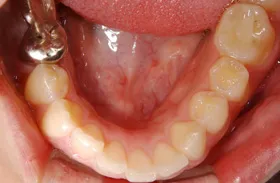

奥歯2本をインプラントで治療したケース

■治療前

■治療後

| 主訴 | 左下の歯が2本なくて咬みにくい 入れ歯はわずらわしいので嫌、金属の被せを白くしたい |

| 治療方法 | インプラント治療+補綴治療 |

| 治療期間 | 約1年 |

| 通院回数等 | 20回位 |

| 費用 | 約150万円 |

| リスク・副作用 | インプラント術後の腫れ・痛み |